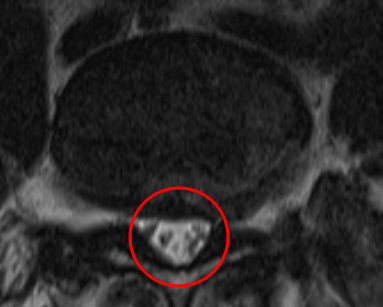

腰痛の原因を調べるため腰椎MRI画像を確認したところ、赤い枠内(L4/5)に椎間板ヘルニアが見つかりました。これが椎間板を圧迫して、腰痛が出てしまっていると考えられます。